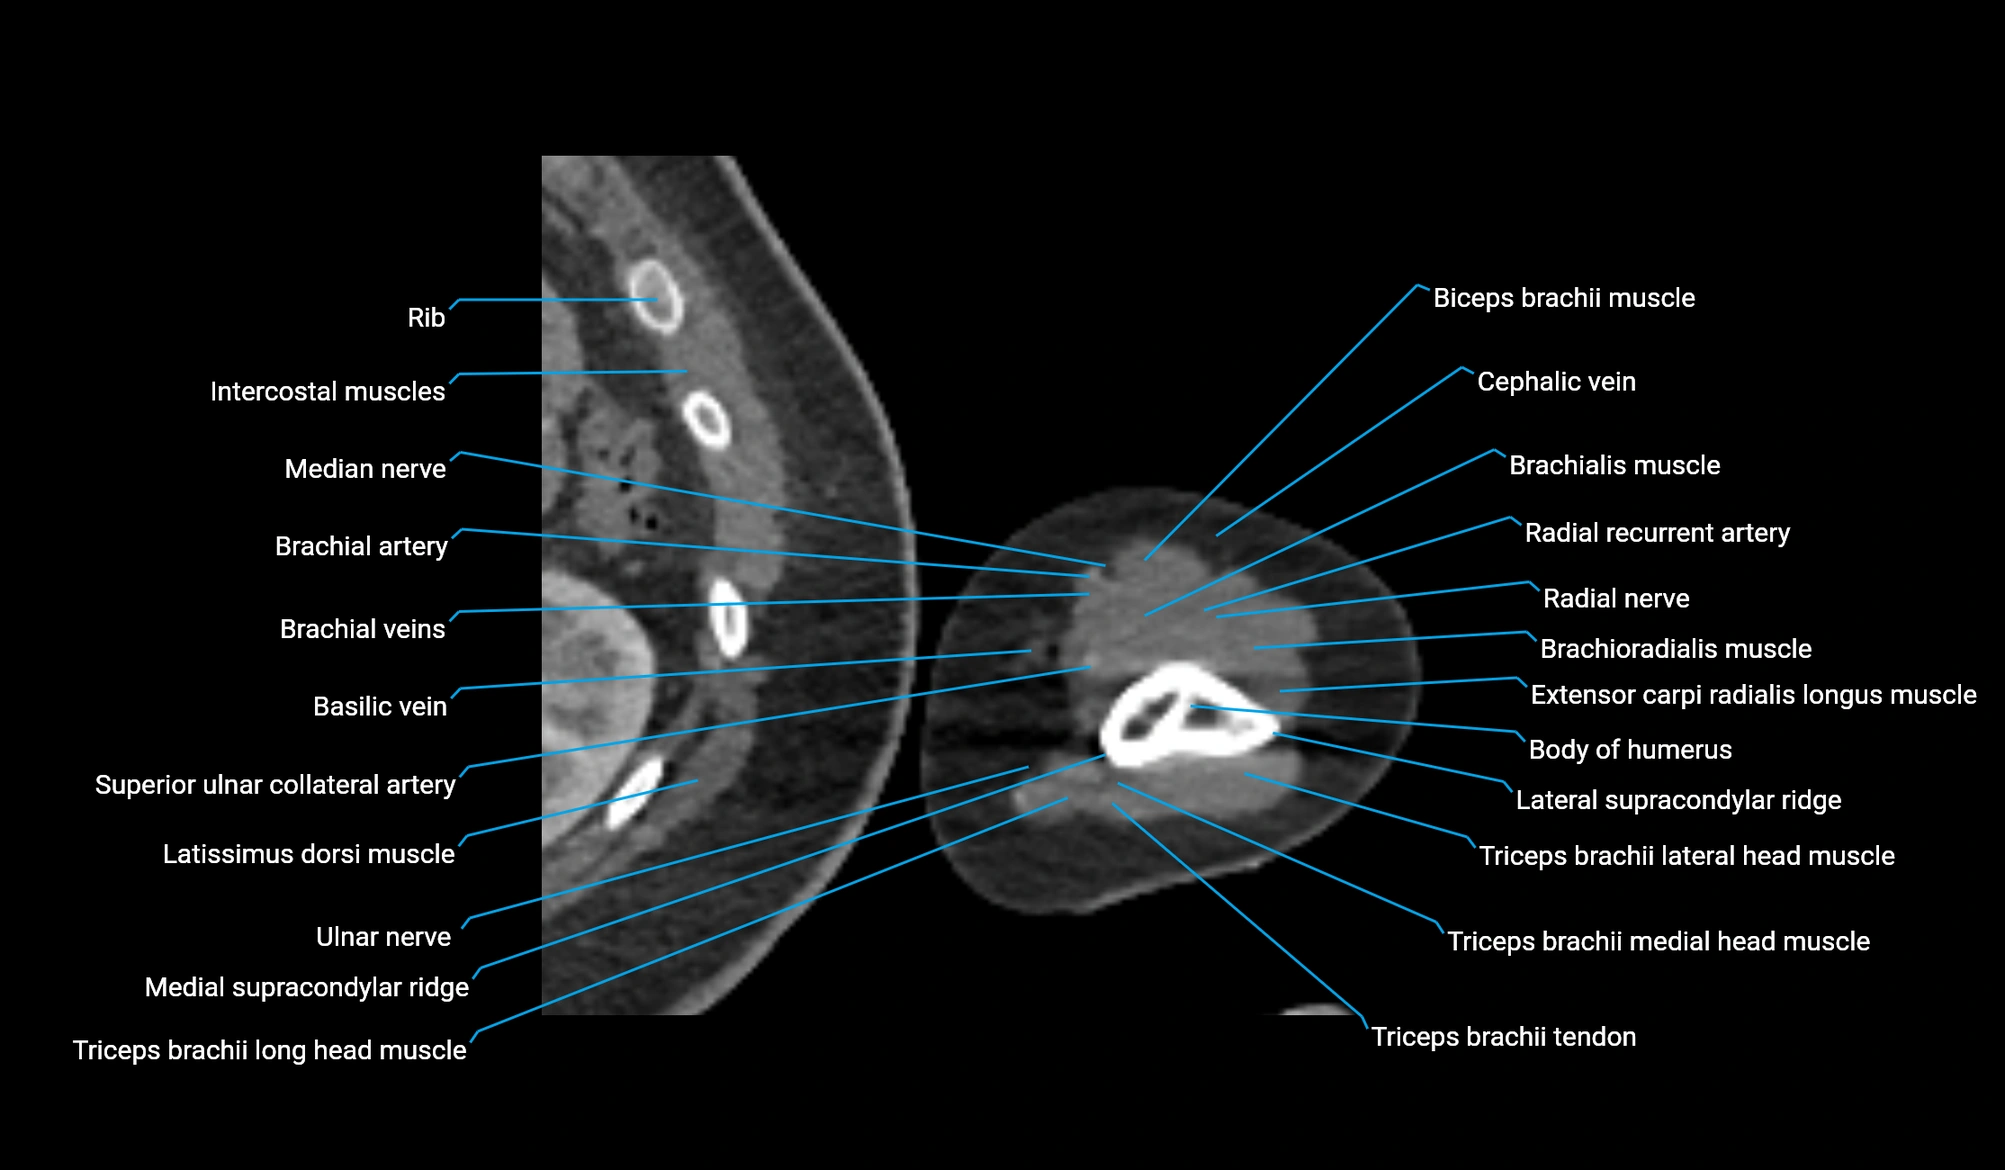

- Basilic vein

- Body of humerus

- Brachial artery

- Brachialis muscle

- Brachioradialis muscle

- Cephalic vein

- Extensor carpi radialis longus muscle

- Lateral head of triceps brachii muscle

- Lateral supracondylar ridge

- Long head of triceps brachii muscle

- Medial head of triceps brachii muscle

- Medial supracondylar ridge

- Median nerve

- Radial nerve

- Radial recurrent artery

- Superior ulnar collateral artery

- Triceps brachii muscle

- Triceps brachii tendon

- Ulnar nerve